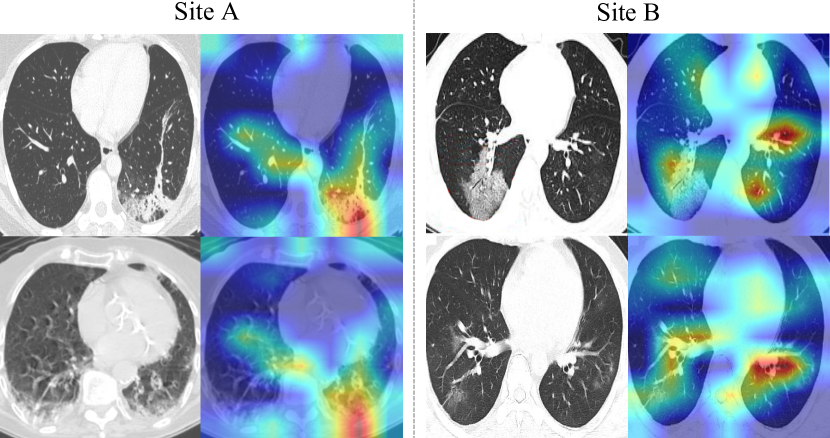

Refer to caption

Figure 4: Visualization of color maps using Grad-CAM [41].

To understand the behavior of our framework, we observe the Grad-CAM [41] visualization results on the two heterogeneous sites, as saliency maps (shown in Figure 4). It is consistently observed on both datasets that the suspicious lesion regions are successfully localized across various abnormality patterns (e.g., bilateral and peripheral ground-glass, and consolidative pulmonary opacity), even with quite mild lesions. This analysis reveals promising interpretability of our classification model trained with image-level labels, demonstrating potential clinical relevance for COVID-19 image-based computer-assisted diagnosis. In addition, we present typical failure cases in Figure 5. We see that the method would mis-classify samples due to wrongly attended regions, and fail to distinguish images with unobvious lesions.